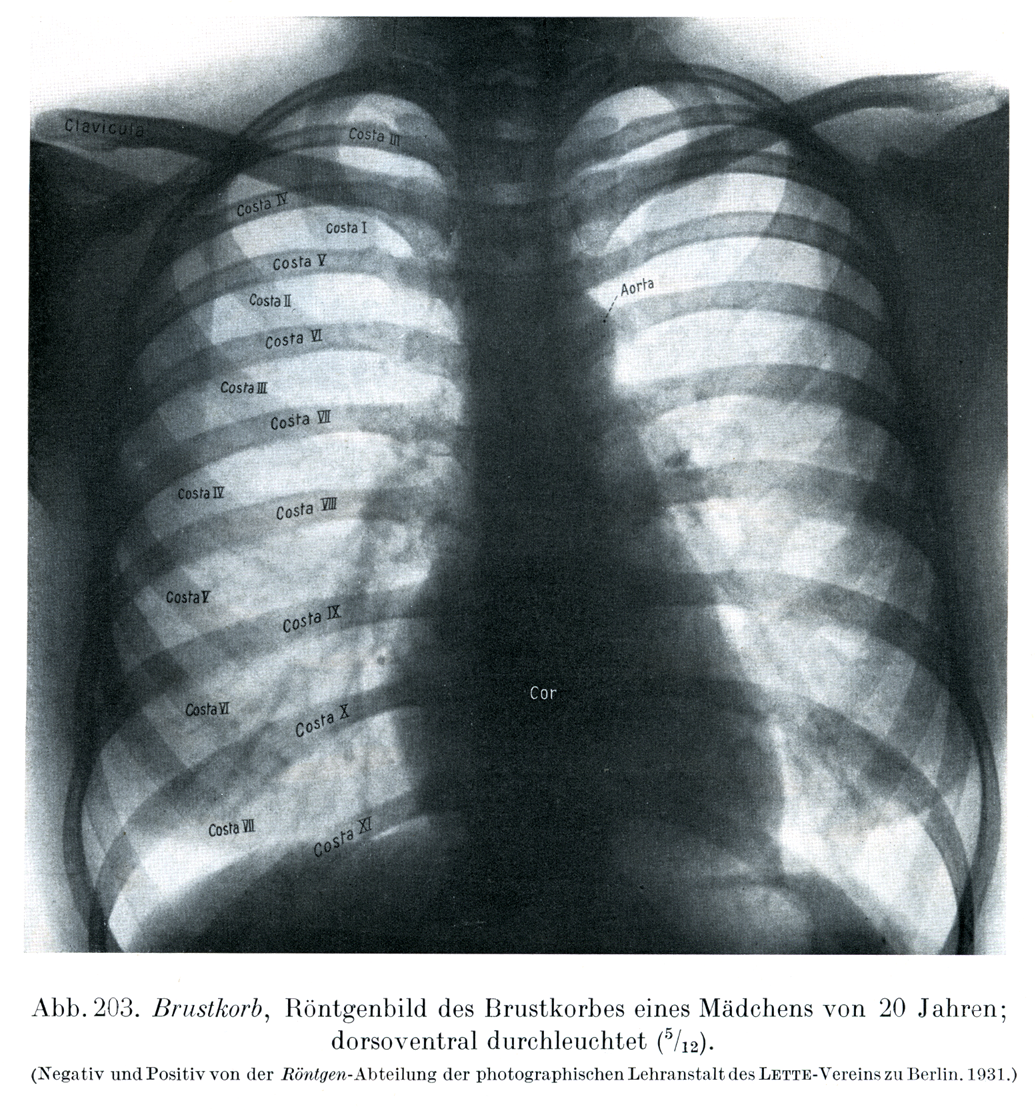

Rauber Kopsch Band1. Abb-203

[図203]20才の少女の

胸郭のレントゲン像

背腹照射(5/12)